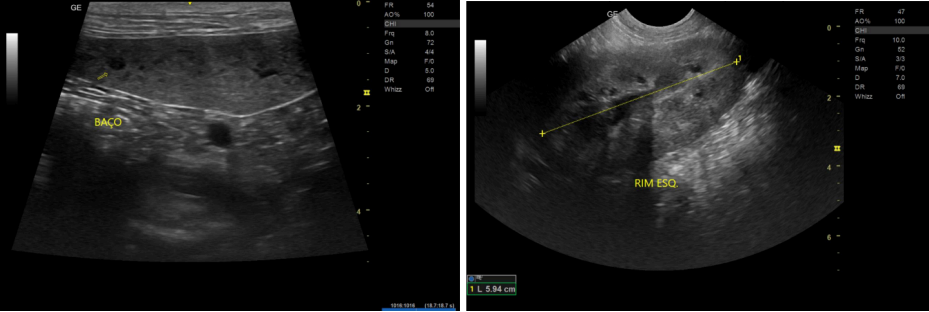

A Tomografia Computadorizada Angiográfica (Angio-TC) evidenciou desvio portossistêmico extra-hepático congênito do tipo esplenorrenal esquerdo, caracterizado por vaso tortuoso originado da veia esplênica e conectado à veia renal esquerda, além da presença de varizes frênicas, indicativas de circulação colateral adquirida associada à hipertensão portal crônica. Este padrão combinado é compatível com casos descritos na literatura em que o shunt congênito evolui com o desenvolvimento de colaterais compensatórias (RICCIARDI, 2016)

Figura 4 – Tomografia Computadorizada Angiográfica de Abdômen Total Contrastado

O caso relatado descreve um cão adulto, SRD, diagnosticado com desvio portossistêmico extra-hepático do tipo esplenorrenal, associado à formação de colaterais adquiridas, entre elas varizes frênicas, configurando um quadro compatível com shunt congênito que evoluiu para hipertensão portal e desenvolvimento de circulação colateral secundária. Esse padrão hemodinâmico já foi relatado em estudos que demonstram a possibilidade de coexistência entre conexões congênitas e vias adquiridas em cães com redução crônica do fluxo portal. Estudos mostram que alguns cães com shunts congênitos desenvolvem varizes colaterais adicionais quando o fígado permanece hipoperfundido por anos (RICCIARDI, 2016; BERTOLINI, 2010; BERTOLINI, 2019).

O baço, no ultrassom, mostrou alterações de ecogenicidade e padrão parenquimatoso alterado. Mesmo que a tomografia tenha descrito dimensões dentro da normalidade, as alterações funcionais vistas no US e a presença de varizes frênicas na tomografia reforçam a ideia de congestão crônica do fluxo esplênico. Na fisiopatologia do shunt esplenorrenal, o sangue que deveria ir para a veia porta passa diretamente pelo vaso anômalo, porém o fluxo não é tão eficiente quanto seria pela porta, devido ao grande volume sanguíneo drenado dos órgãos abdominais e ao calibre do vaso não ser suficiente para suportar tamanho volume sanguíneo. Isso causa lentificação na drenagem e mudanças texturais no baço, como já descrito por Bertolini (2019). O conjunto entre achado ultrassonográfico e a região de microvasos neovasculares observada na TC sugere que o baço realmente estava participando de um processo de angiogênese devido a congestão sanguínea causada pela lentificação na drenagem, com um remodelamento vascular para suprir essa pressão sanguínea.

A tomografia computadorizada (TC) com contraste foi essencial para a definição diagnóstica, permitindo a visualização detalhada do shunt esplenorrenal e das varizes frênicas associadas. Estudos demonstram que a TC apresenta sensibilidade e especificidade superiores quando comparada à ultrassonografia, sendo considerada o padrão ouro para detecção, caracterização anatômica e planejamento cirúrgico dos DPSEH (KIM et al., 2013; ZWINGENBERGER et al., 2005; POSASTIUC et al., 2022). A presença de vasos colaterais adquiridas no exame tomográfico reforça a hipótese de hipertensão portal crônica, concordando com relatos que descrevem padrões semelhantes em cães com alterações vasculares prolongadas (BERTOLINI, 2010; 2019).